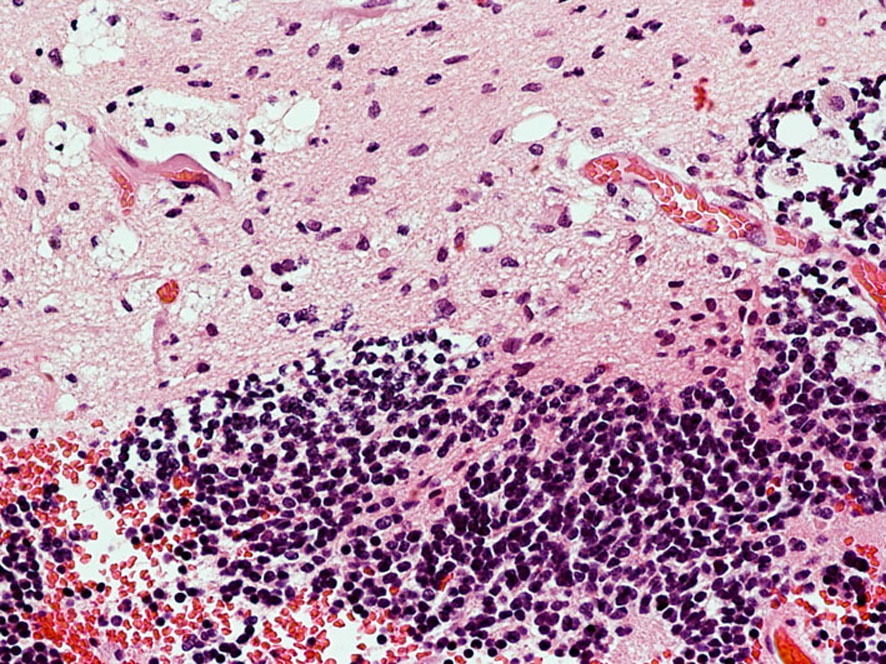

乳児の髄芽腫の治療後の硬膜血管腫

生後8ヶ月で髄芽腫を発症して,手術後に8コースの化学療法して,残存腫瘍があったために2歳半で脳脊髄照射18グレイと後頭窩局所照射21.6グレイをしました。放射線治療後2年で見つかった左前頭部腫瘍です。てっきり脳表播種再発かと思いましたが,良性の硬膜血管腫でした。この子は20歳となり再発もなく元気です。幼児期の放射線治療あるいは化学療法は,予想より早期に,珍しい2次腫瘍を誘発することがあると考えたほうがいいのでしょう。この腫瘍の部位には1日線量1.8グレイで18グレイしか照射されていませんでした。